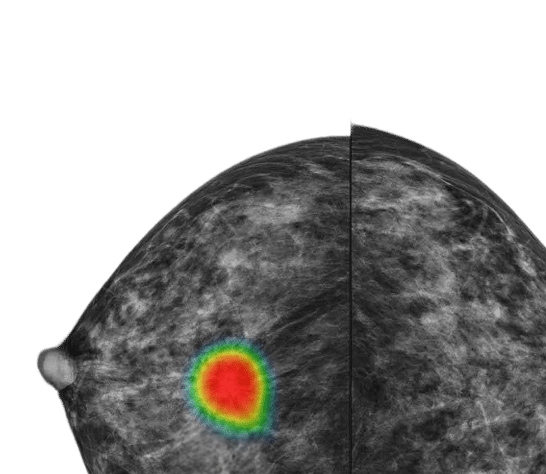

루닛 인사이트 MMG는 유방 촬영 영상을 분석해 유방암 의심부위의 위치와 유방 내 병변이 존재할 가능성을 0~100 범위의 점수로 표시합니다.

또한 병변 유형을 세 가지로 표시합니다.